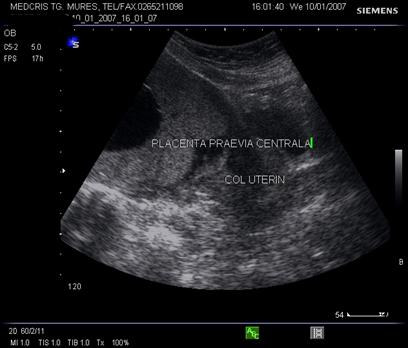

IV: placenta praevia centrala (completa): intreg orificiul cervical intern este acoperit de masa placentara.

Diagnosticul ecografic se face urmarind marginea placentara inferioara si raportul cu orificiul cervical intern. O imagine mai buna necesita vezica urinara in semipletie sau chiar o ecografie transvaginala.

Fig. nr.218. Placenta praevia complet centrala , la aceeasi sarcina ca in figura precedenta, dar la 28 saptamani gestationale